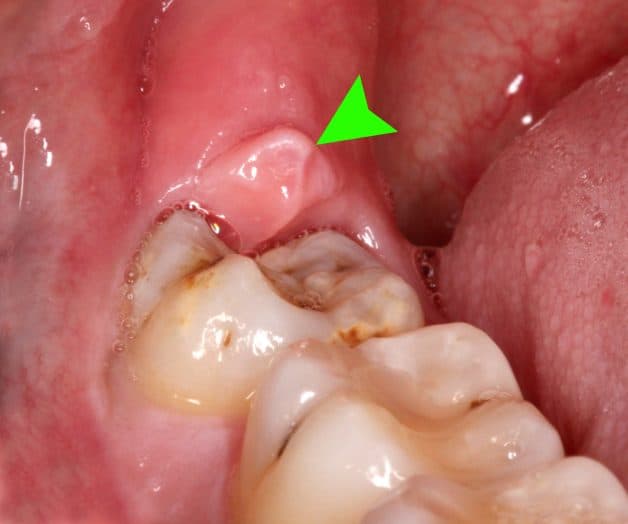

Viêm lợi trùm là biến chứng xuất hiện khi răng khôn của bạn mọc bất thường

2.1 Lợi bị sưng đỏ

Phần lợi ở trên răng khôn bị sưng đỏ. Khi ấn vào phần lợi đó sẽ có cảm giác đau. Nhiều trường hợp còn có mủ và chảy nước.